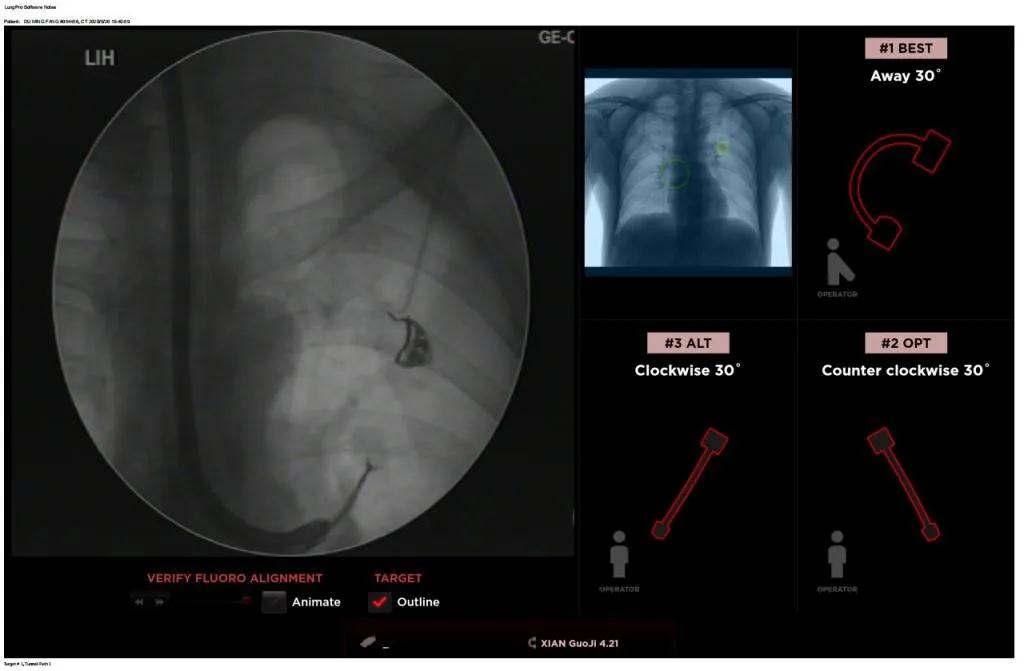

西安國際醫(yī)學中心醫(yī)院呼吸內(nèi)科完成西北地區(qū)首例LungPro全肺導航系統(tǒng)引導下BTPNA手術(shù)

近日,西安國際醫(yī)學中心醫(yī)院胸科醫(yī)院歐陽海峰副院長完成西北地區(qū)首例LungPro全肺導航系統(tǒng)引導下經(jīng)支氣管鏡跨肺實質(zhì)肺外周結(jié)節(jié)活檢術(shù)。

經(jīng)過充分的討論后,歐陽海峰副院長決定為患者實施LungPro全肺導航系統(tǒng)引導的經(jīng)支氣管跨肺實質(zhì)肺外周結(jié)節(jié)活檢術(shù)。Broncus導航系統(tǒng)LungPro具有全球領(lǐng)先獨創(chuàng)的BTPNA技術(shù)(支氣管鏡下跨結(jié)節(jié)抵達術(shù)),可以實現(xiàn)對氣道外周孤立性肺小結(jié)節(jié)的精準定位,建立直接通往氣道外病變部位的通道,以實現(xiàn)全肺的診斷及后續(xù)治療。這項技術(shù)不僅彌補了現(xiàn)有支氣管鏡技術(shù)由于受限于病變部位是否有氣道可通向以及無法準確定位病變部位而造成的較低診斷率,同時還彌補了CT引導下經(jīng)胸穿刺(TTNA)無法適用于某些特定部位如中央及肩胛骨等結(jié)節(jié)的問題,并且還避免了經(jīng)胸穿刺給患者帶來氣胸、出血的高風險,可有效提高肺部結(jié)節(jié)及早期肺癌診斷陽性率,亦可用于早期肺癌的射頻消融或微波治療,具有微創(chuàng)、安全、同期雙肺診療等優(yōu)勢。

團隊術(shù)前進行了精心的準備,通過高分辨率CT建立了導航路徑,在麻醉科手術(shù)室的配合下,借助LungPro引導順利的確定了病灶部位、建立隧道并實施活檢,術(shù)后患者恢復順利出院。